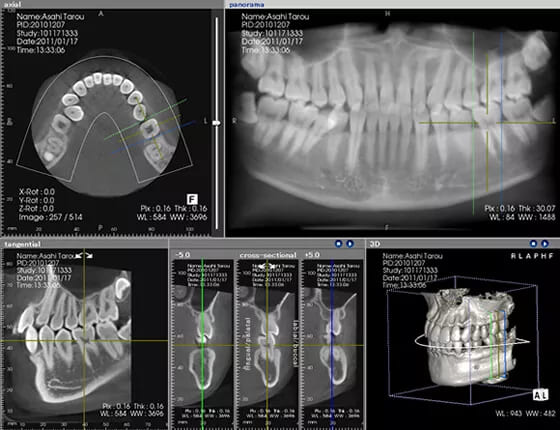

CT/レントゲン検査

歯周病は顎の骨を溶かしてしまう病気です。その進行状況を正確に把握するために、CT検査を行います。CTは3Dで立体的な画像を撮影できる装置で、歯周病の進行度を詳しく調べることができます。

当院では、CT撮影による骨の状態の報告や、術前術後の状態を写真でお見せするなど、さまざまな情報提供ツールを活用して、患者様が納得できるまで丁寧に説明を行っています。

歯周病治療には継続的な治療が重要ですが、忙しくて通院が難しい方には、ライフスタイルに合わせた治療計画をご提案します。当院では「短期集中治療」を行っており、ポイントは「1回の治療時間を長く取る」ことと、「精密機器のフル活用」です。

治療前に検査を行い、治療の全体の工数を明確にしたうえで、通常は何度か通院が必要な治療を1回でまとめて行います。また、CTなどの精密機器を使用することで、治療時間と期間を短縮し、効率的に治療を進められます。歯周病だけでなく、歯科治療全般に関しても、通院回数を減らしたい方には最適な治療方法をご提案します。少しでも不安な点があれば、どんな些細なことでもお気軽にご相談ください。